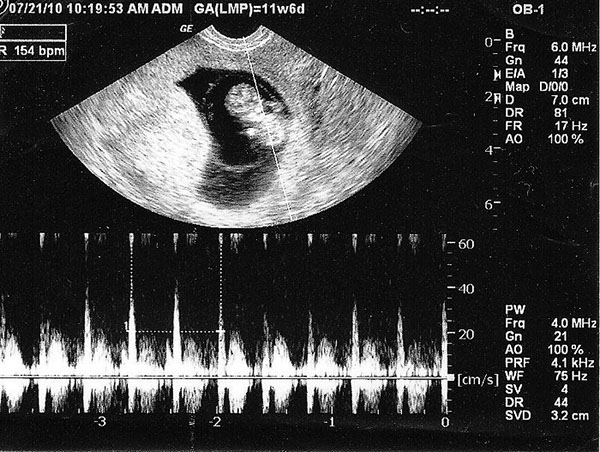

Lúc này tim thai đã chia thành 4 ngăn với nhịp 100 đến 160 nhịp/phút, nhịp tim sẽ bắt đầu giảm đi từ tuần thứ 10 cho đến khi sinh. Vì thế bạn không cần lo lắng khi tim thai của bé đập nhiều hơn người trưởng thành, đây là chuyện hết sức bình thường.

Khi đi siêu âm, mẹ sẽ được bác sĩ thông báo các chỉ số của thai nhi, thông qua các chỉ số này bác sĩ có thể kết luận bé có đang phát triển khỏe mạnh hay không. Thông thường một em bé phát triển khỏe mạnh thì các chỉ số sẽ đạt đến mức tiêu chuẩn như sau: Đường kính túi thai 30mm, chiều dài đầu mông 16 đến 22mm, tim thai 100 đến 160 nhịp/phút.

Bác sĩ sẽ siêu âm thai 8 tuần thông qua kĩ thuật siêu âm 2D vì các chỉ số khá cơ bản, chỉ cần sử dụng phương pháp này là đủ. Các đợt khám thai sau đó thì siêu âm màu, 3D, 4D… sẽ được áp dụng tùy theo các loại chỉ số cần đo.